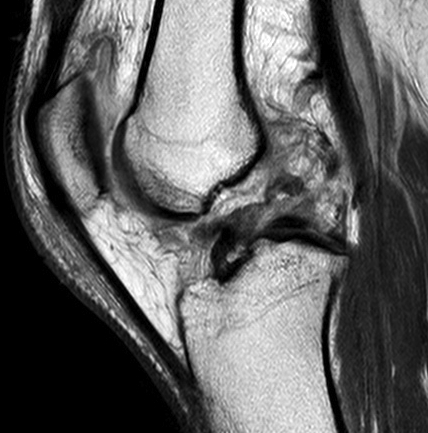

Medial dimpling Entrapped vastus medialis post knee dislocation on Coronal and Sagittal MRI

Sagittal MRI demonstrating patella tendon avulsion and ACL / PCL tear

Sagittal MRI demonstrating complete tear of ACL and mid substance tear of PCL